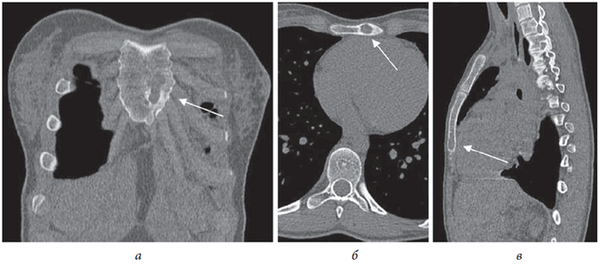

Поводом к направлению пациентки в СПбНИИФ стало подозрение на туберкулезный остит тела грудины, высказанное на основании результатов компьютерной томографии грудной клетки, на которой выявлена деструктивная полость размером 21 × 11 × 10 мм в дистальном отделе тела грудины с четким, частично склерозированным контуром в нижнем отделе и интактными окружающими мягкими тканями (рис. 1).

Рис. 1. Больная П., 17 лет. КТ-срезы грудной клетки (костный режим): а — фронтальный, б — аксиальный и в — сагиттальный. Стрелкой указана полость деструкции в теле грудины